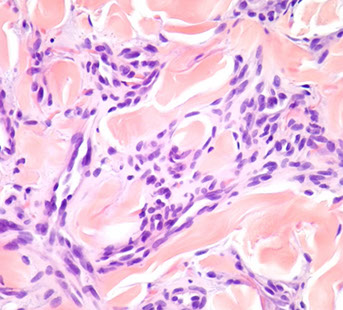

Angiosarcoma

Bland-appearing angiosarcoma with multilayered endotheliom that infiltrates (splits) through collagen

Rare tumor in adults, (<1% of sarcomas), ~7th decade (very rare in kiddos) derived from endothelial cells of blood vessels that can occur in multiple sites depending on type of risk factor exposure

Micro: atypical vascular spaced lined by endothelial cells c atypia and multilayering that involves subQ and has RBCs in intracytoplasmic lumina in more solid areas

- lots of mits and necrosis

IHC: (+) Factor 8 related peptide, CD31, Ki-67, FLI-1, thrombomodulin, CD34, c-kit, VEGFR-3, ERG, INI-1 (is lost in epithelioid sarcoma)